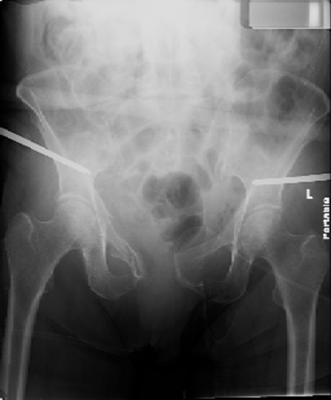

attached are images of a 70 year old female after peds versus car. her own car ran her over.

injuries are limited to the pelvis. left rami open and visible in a 10cm vertical laceration just lateral to left labia majora. wound is grossly clean. no vaginal and no urinary issues. CT scan shows widening of both SI joints anteriorly but I think this is vertically stable pattern.

pt treated that night with I/D and supra-acetabular frame to close the ring. consideration was given for SI screws bilateraly, but given time of night and other factors decision made not to proceed.

so the question is what next operatively if anything? concerns are infection, nonunion anteriorly and possible incompetence of the pelvic floor which may lead to prolapse issues. right rami are comminuted and plating may entail ilioinguinal approach to extend plate laterally to right iliac wing. retrograde screw up right rami is an option but I am not convinced it will add much. adding SI screws very doable, but major concern is restoring anterior ring. so far wound is clean and closed over a drain, and I have no plans to open it back up and wash again.

maintaining pelvic alignment in ex-fix in 70 yo female for any length of time may be challenging.

any thoughts? would anyone plate the pubic symphysis to close the gap and leave the more lateral rami fractures alone? the most recent pelvic case on this website involved pts with suprapubic catheters and antibiotic options including resorbable beads. I wonder how many people would plate and place antibiotic beads. thanks.

attached are several CT cuts. please let me know if you need more. the CT is pre-pelvic ex-fix placement.

Thank you.

I wouldn't plate the front.

But I would add screws posteriorly.